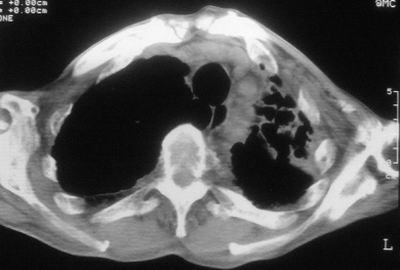

标题: CT11864:男,47岁,反复咳嗽、咯痰、咯血3年,请分析. [打印本页]

患者,男,47岁,反复咳嗽、咯痰、咯血3年,再发5天。痰培养未找到真菌、抗酸杆菌、癌细胞。

左肺上叶体积明显缩小,其内见多发透光区,纵隔向左侧移位,左肺下叶多发班片状病灶,边界模糊,1左肺上叶先天肺发育不全,2左肺下叶肺炎,

左肺上叶结核伴肺纤维化,纵隔移位,左肺下叶感染性病变,建议抗炎抗结核后复查,双肺气肿.

考虑:左肺慢纤伴霉菌球形成、双肺全小叶型肺气肿。

1)考虑为:左肺上叶肺结核(空洞形成),伴左下肺感染;不排除霉菌感染可能。2)肺气肿。

左肺上叶结核伴肺纤维化空洞形成并左肺下叶感染,纵隔牵拉移位,建议作进一步检查排除左侧肺霉菌感染可能。